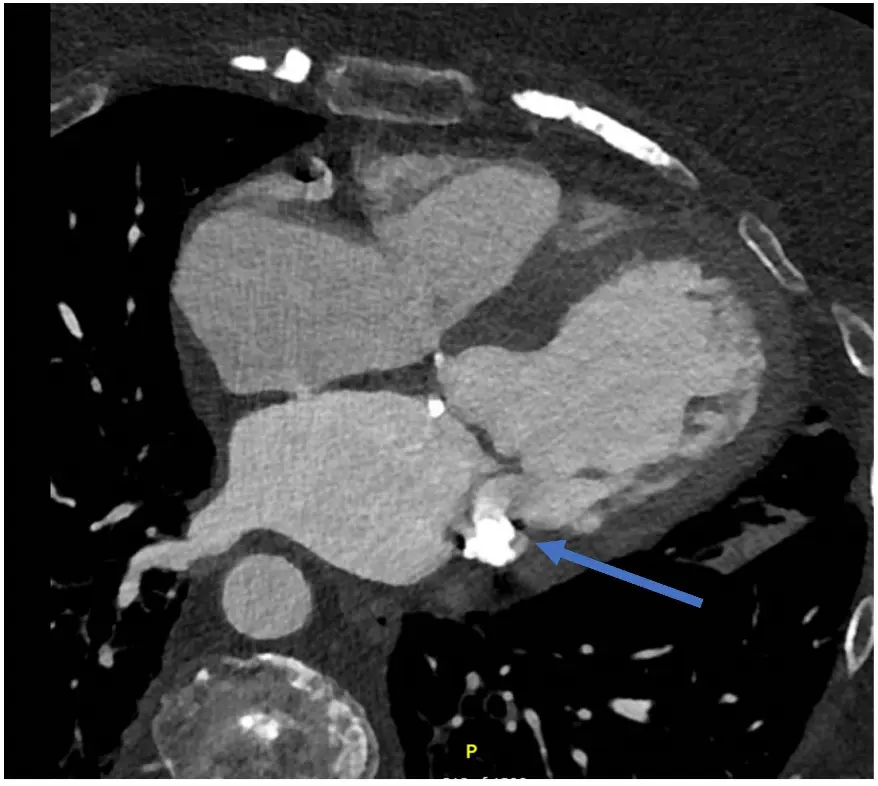

Cardiac computed tomography (CT) has emerged as a complementary modality for the structural assessment of FMR, providing high-resolution, three-dimensional visualization of the entire mitral apparatus—including the annulus, leaflets, chordae, and papillary muscles—with submillimeter spatial accuracy (Figure 7 and Figure 8) [108]. While three-dimensional echocardiography remains central to FMR evaluation, CT is widely regarded as the reference standard for mitral annular quantification and offers unique advantages in characterizing complex mitral geometry [109]. Multiphase CT reconstructions allow precise assessment of annular area, inter-commissural and septo-lateral diameters, annular nonplanarity, leaflet length, tenting height, and papillary muscle position throughout the cardiac cycle [110,111].

Figure 7. Cardiac Computed Tomography (CT) for Anatomy Evaluation. CT cardiac offers good temporal and spatial resolution for evaluation of cardiac structures and understanding the FMR mechanism and leaflet anatomy (including annulus, any mitral annular calcification, relation to LVOT). This image shows left atrial dilatation and LV dilatation. There is evidence of mitral annular calcification (indicated by the blue arrow).